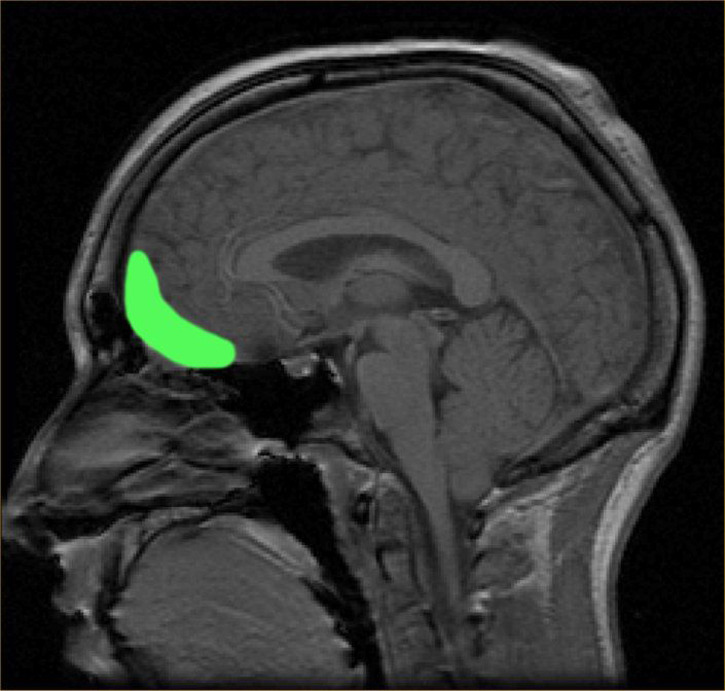

It has recently been discovered that there may be a neurological basis to beauty. This was found when brain images of people familiar with mathematics were compared with people who were shown beautiful art or music.

In the study, published earlier this year, researchers at the University College of London analyzed the brains of 15 mathematicians as they viewed 60 mathematical formulae, using magnetic resonance imaging (MRIs). The subjects were tasked with rating each formula on how beautiful they perceived it to be.

Then, the researchers observed that different areas of the brain were activated, depending on whether a formula was considered to be beautiful, ugly or neutral.

They found that the experience of mathematical beauty activated the same part of the emotional brain, mainly the medial orbitofrontal cortex -- the same areas triggered by music and art!

This study highlights the fact that math is a very beautiful thing! The most beautiful formulae were found to be Euler’s identity and the Pythagorean identity. Can aesthetic experiences be quantified? The answer appears to be: Yes!

- Photo: by Paul Wicks. Medial Orbitofrontal Cortex Reacting to Beauty in Math.